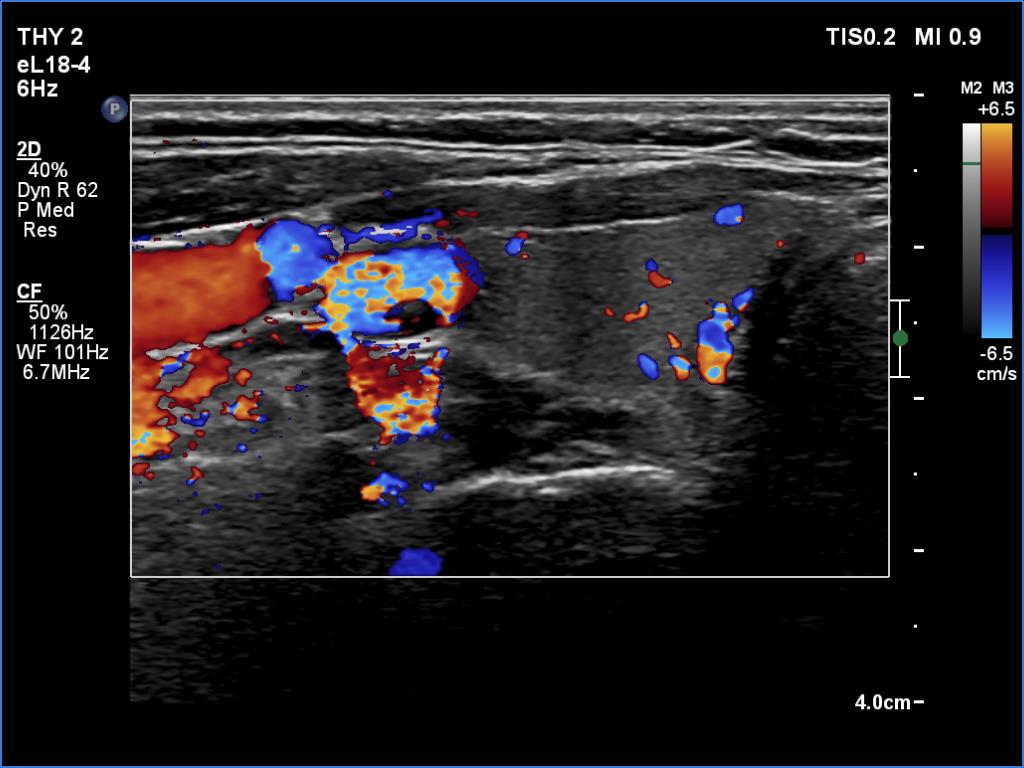

Ultrasonography. The thyroid was echonormal. There were no discrete lesions. The vascularity was average or slightly decreased. Microflow imaging has not revealed increased number of intrathyroidal vessels.